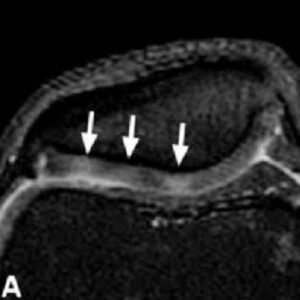

Chondromalacia patellae grades II–IV in various patients.

(A) Axial fast spin echo proton density fat saturated (FSE PD FS) MR image of chondromalacia patellae grade II in a 46-year-old male. High signal is seen in the patellar cartilage in the lateral patellar facet (arrows).